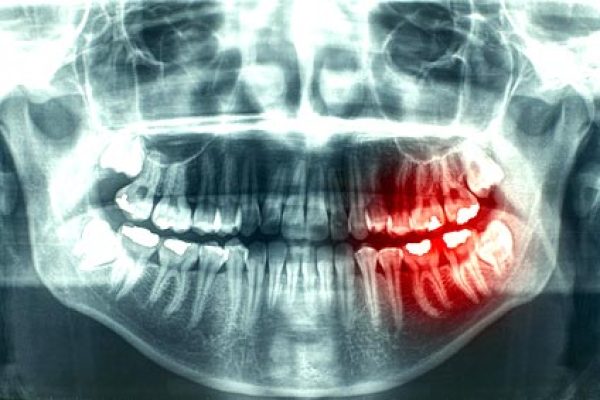

治療前

治療後

治療結束後,可見下顎已恢復至正常位置